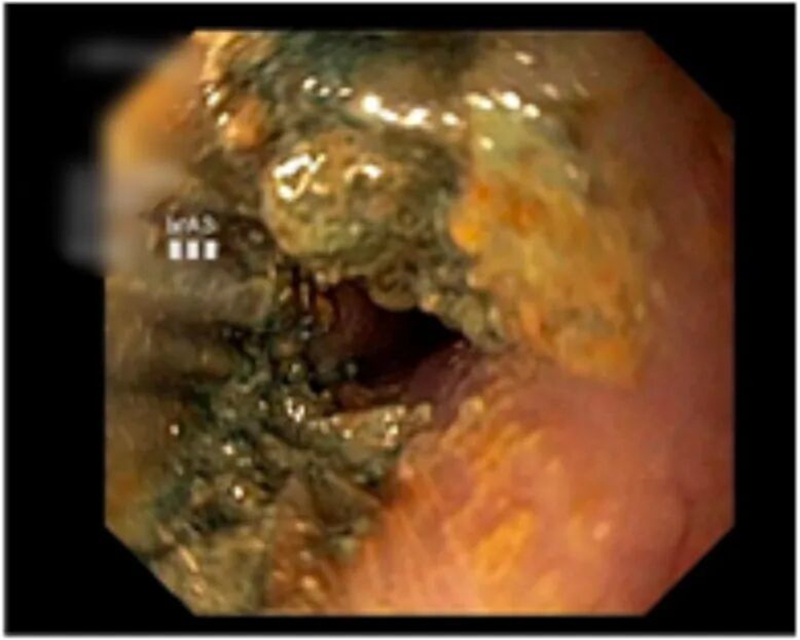

医院近期取出的消化道异物

其中,3岁以下幼儿更是高危群体。这个年龄段的孩子好奇心旺盛,习惯用嘴巴探索世界,且吞咽反射尚未发育完全,像纽扣电池、磁力珠、坚果这类不起眼的小物件,一旦被误吞,很可能造成不可逆的严重伤害。轩轩的遭遇,也再次给广大家长敲响了安全的警钟:做好防护,让孩子远离这类潜在伤害。